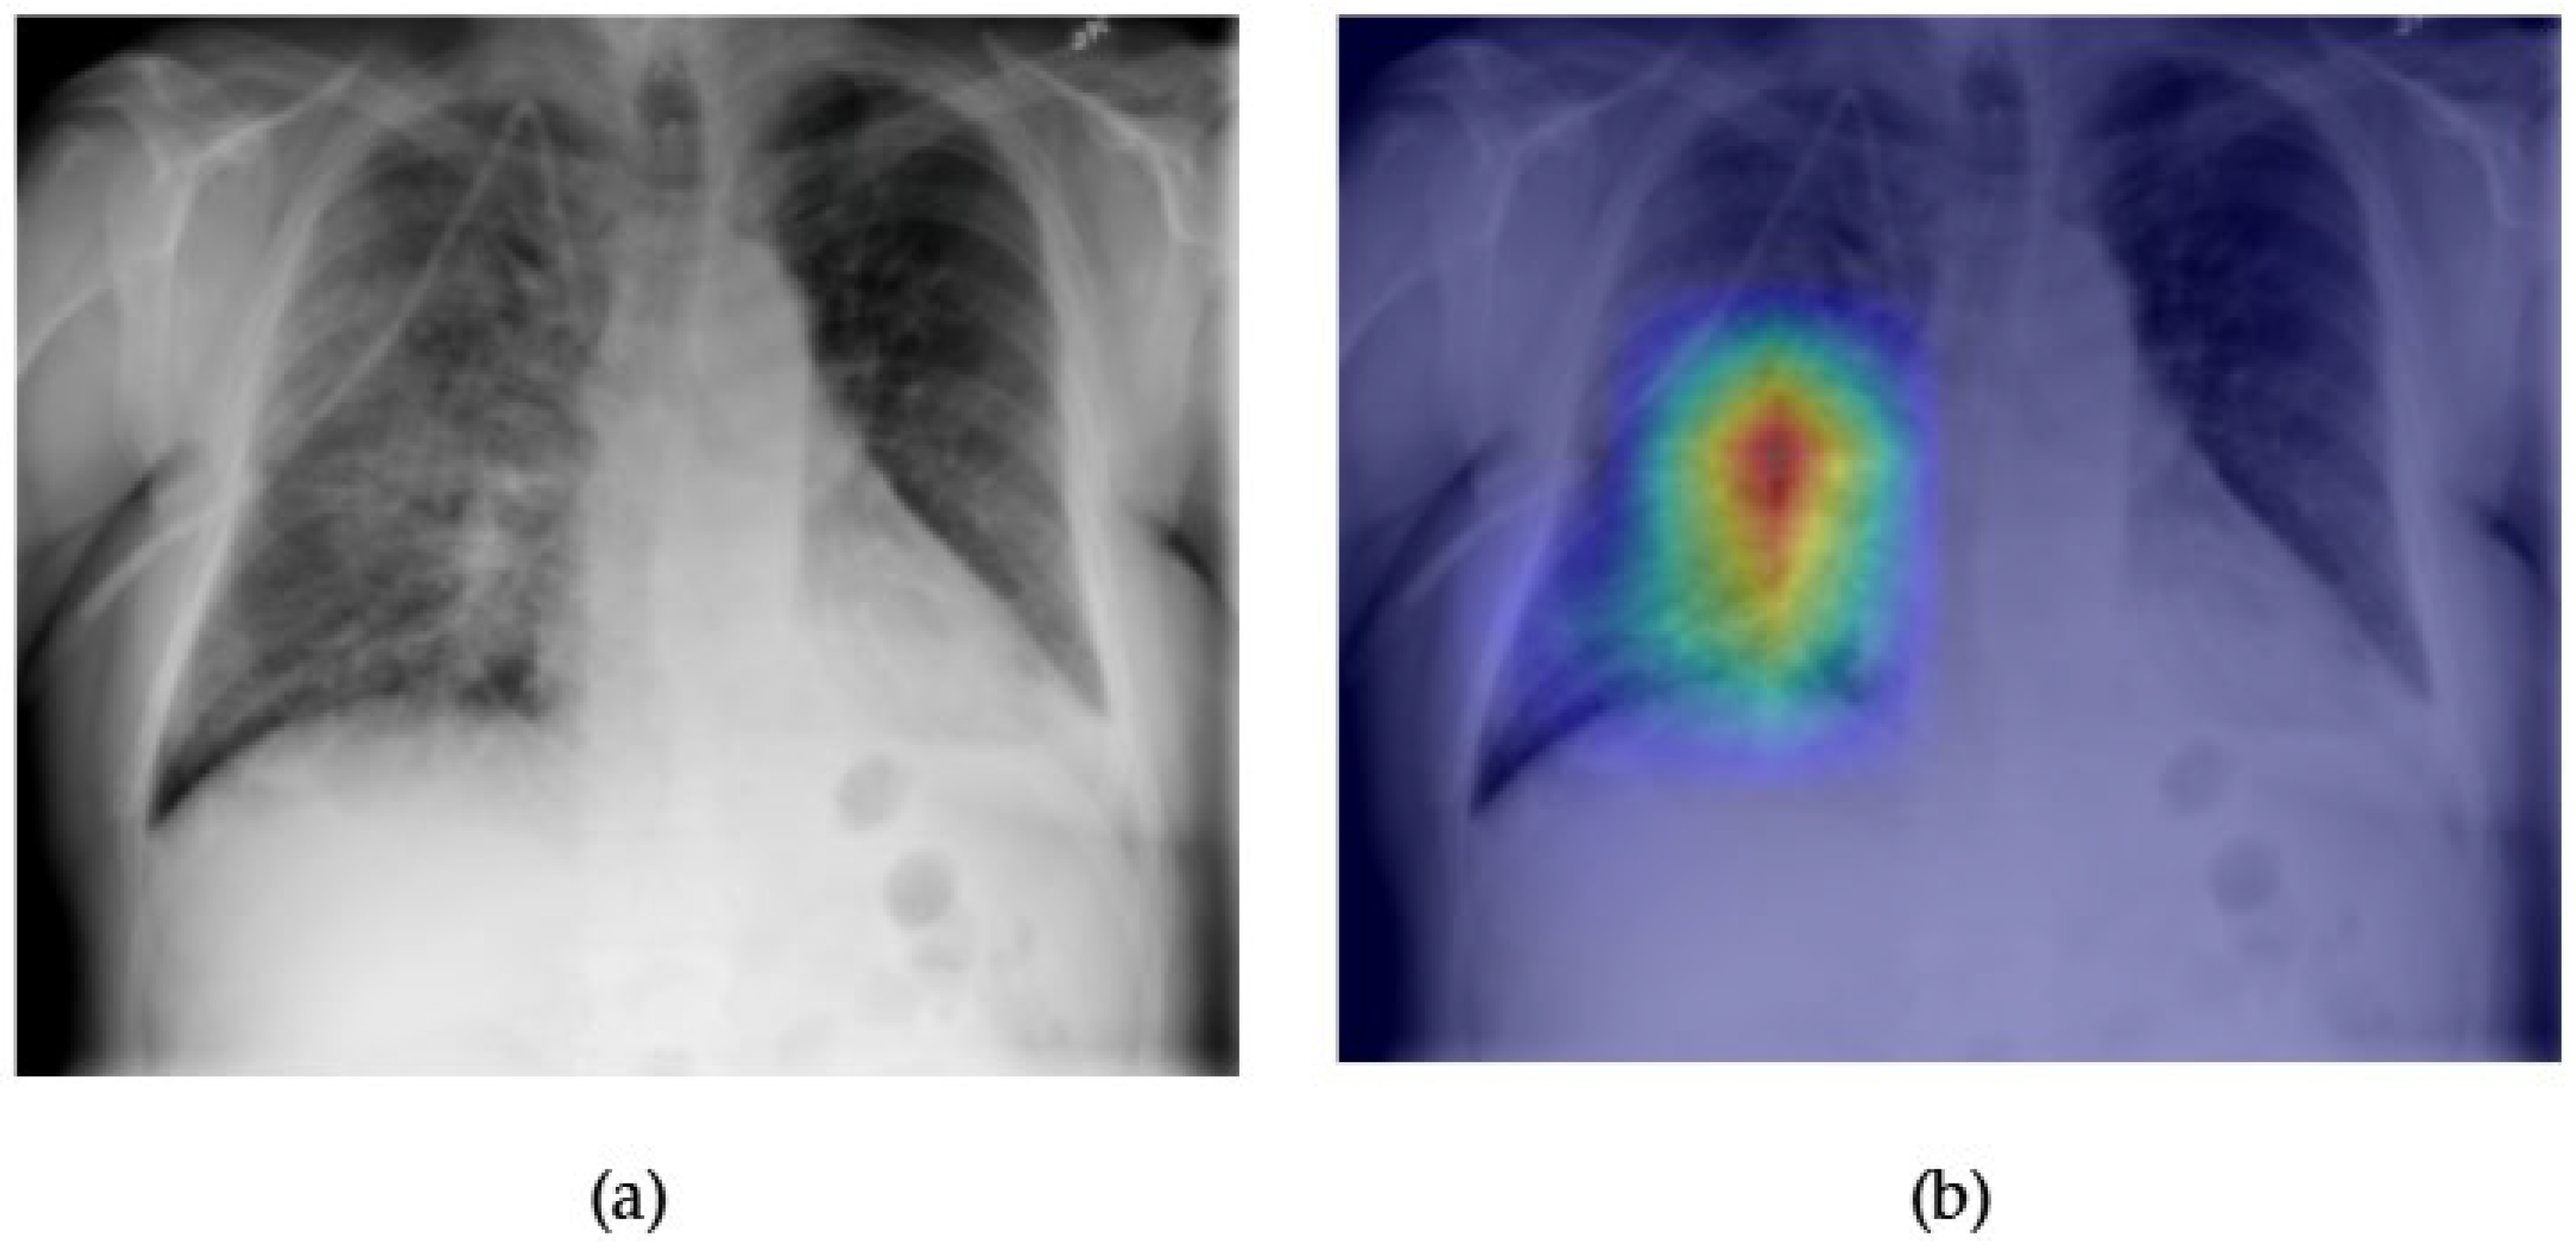

- Although our Grad-CAM-based explainability provides useful localization cues, it is inherently limited by its post hoc nature and reliance on gradient flow from the final convolutional layers. Future research could incorporate advanced interpretability techniques such as Layer-wise Relevance Propagation (LRP), Integrated Gradients, or attention rollouts in Transformers, which may offer a more complete understanding of model reasoning.